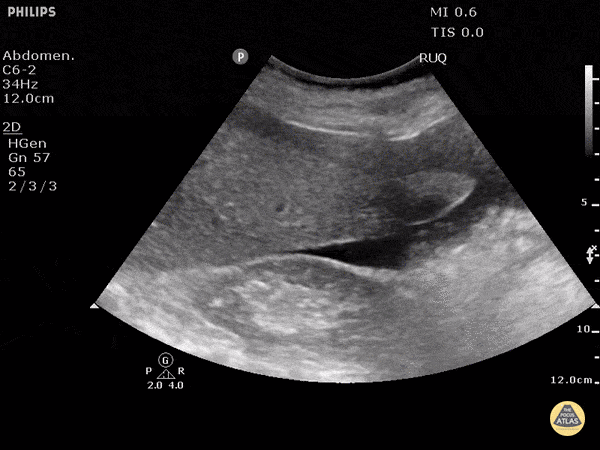

Trauma - Positive FAST - RUQ - Morison's Pouch

Blunt trauma patient with POSITIVE FAST scan. The liver can been seen floating in free fluid with the kidney posteriorly. The fluid is in Morison's pouch. Be sure to visualize the tip of the liver to complete the evaluation. Dr. Justin Bowra